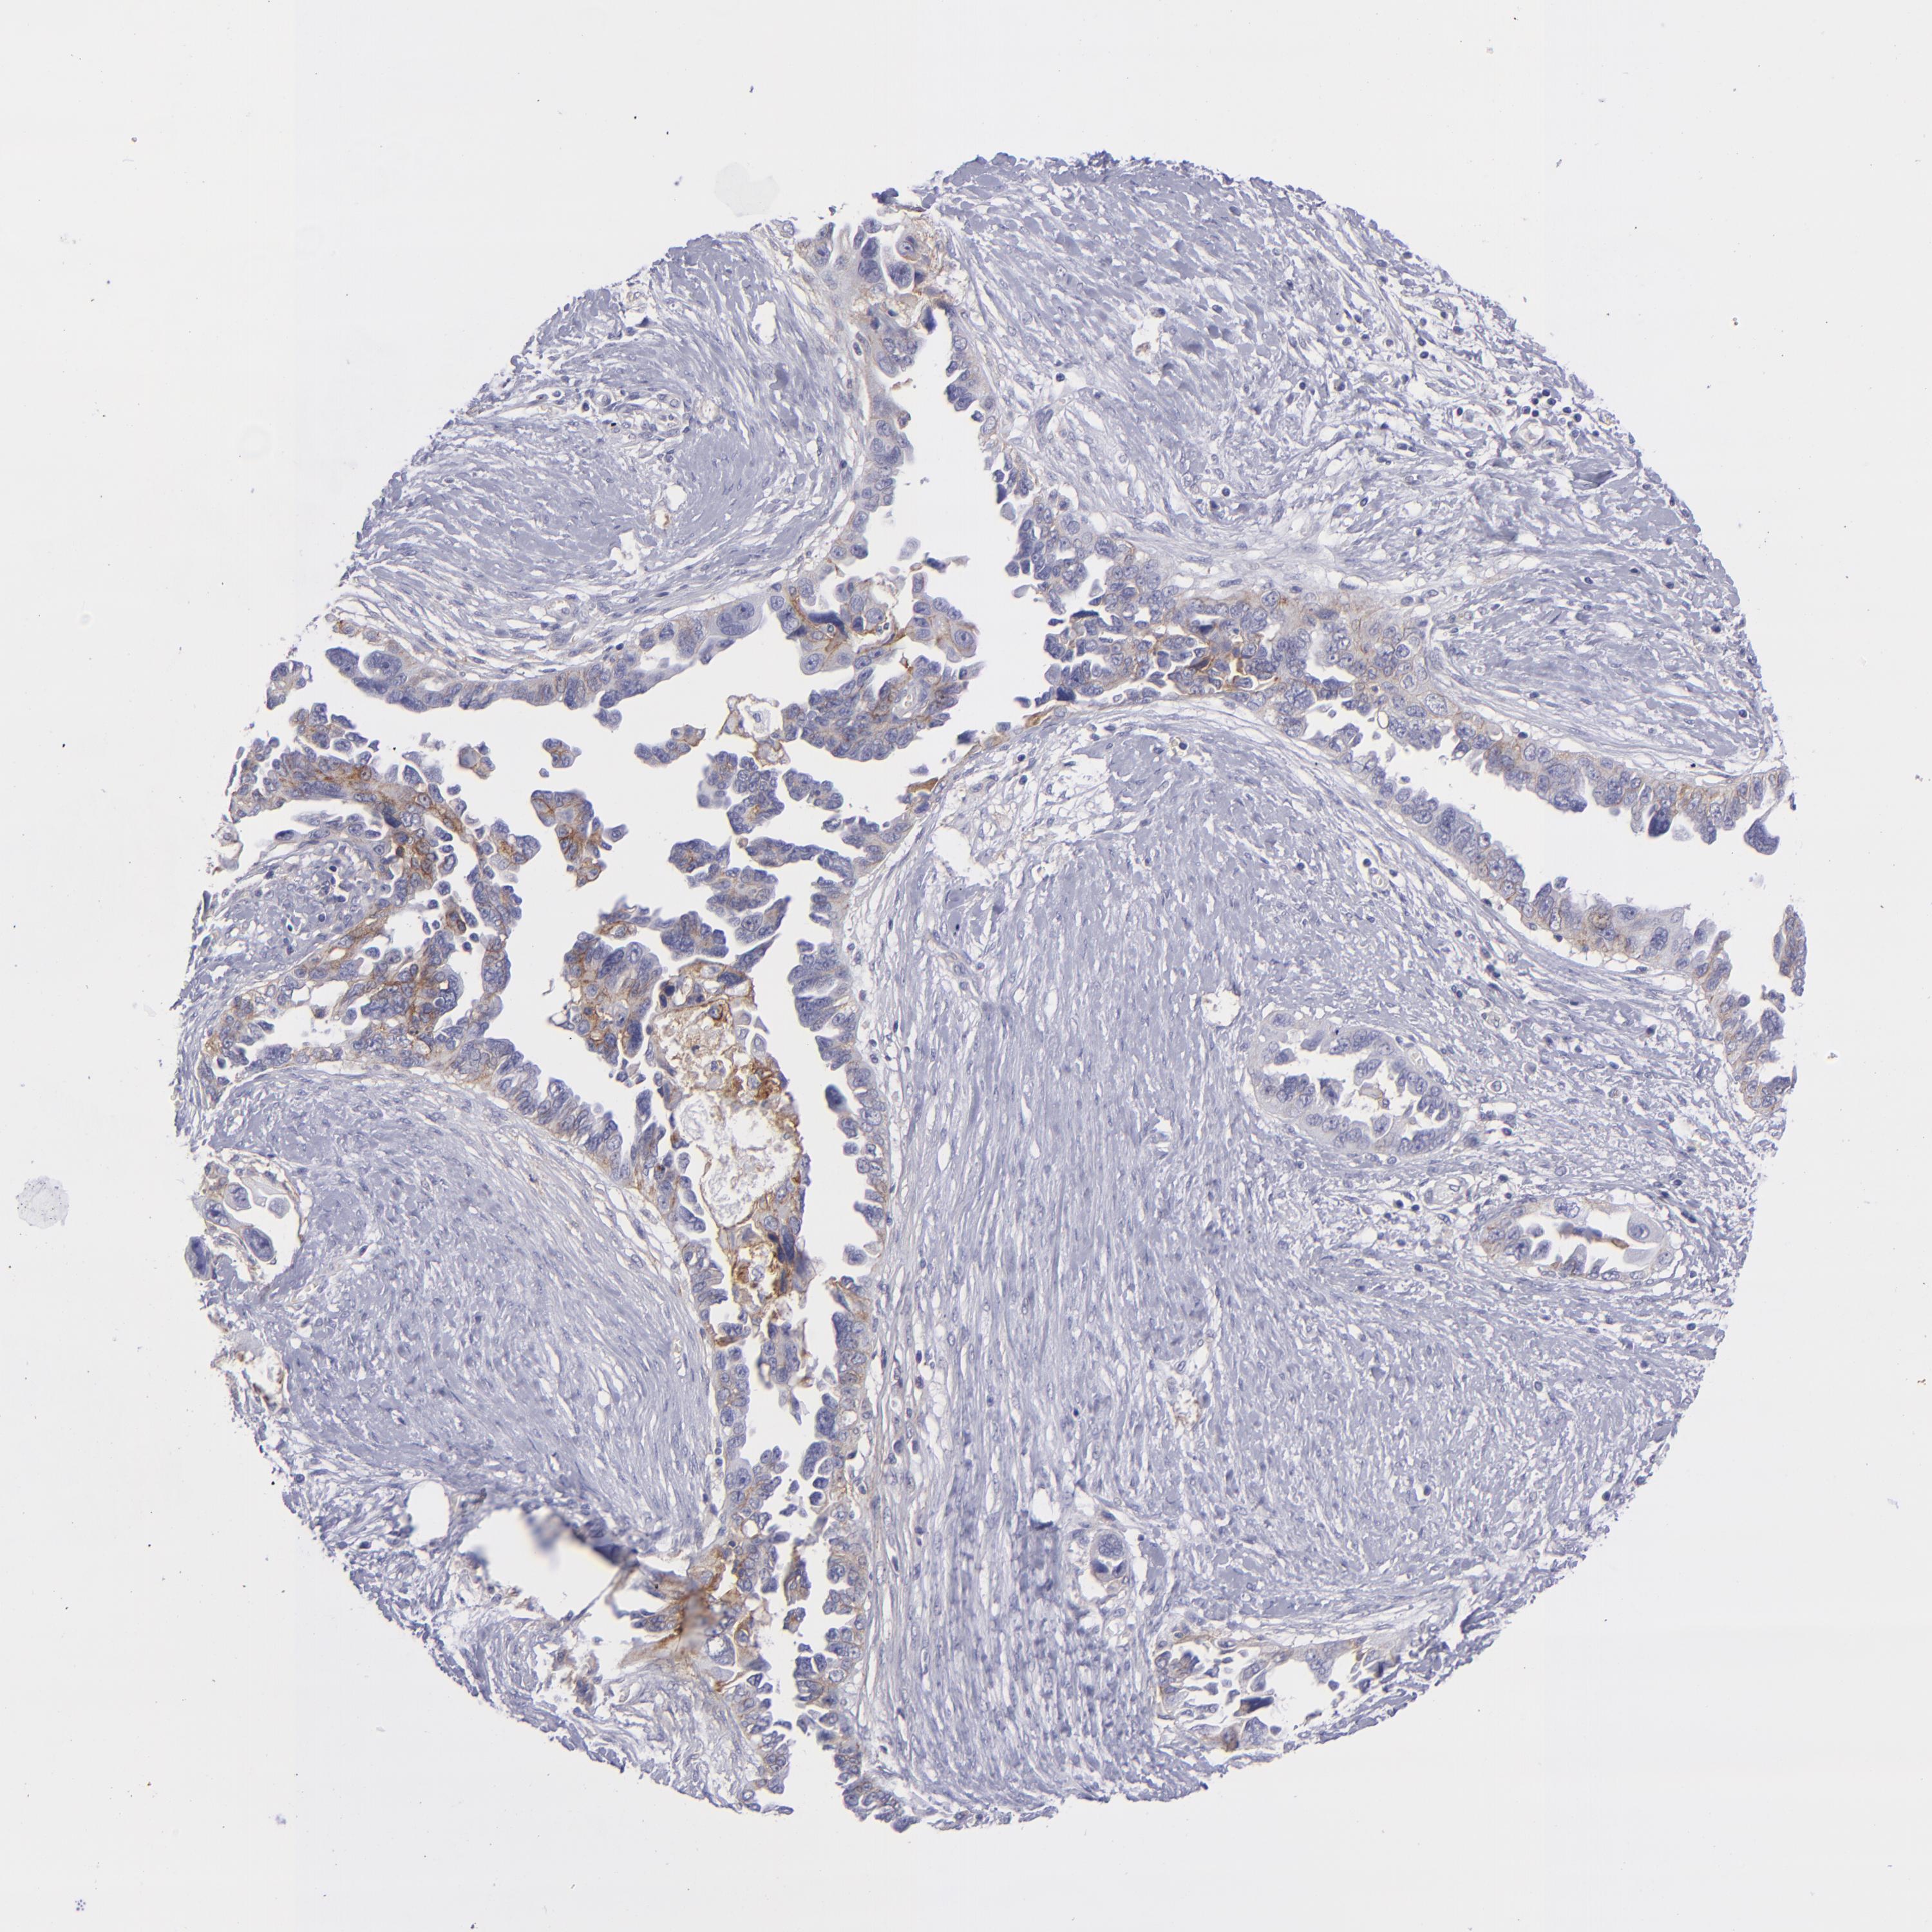

OVARIAN CANCER - Protein expressioni

A mouse-over function shows sample information and annotation data. Click on an image to view it in a full screen mode. Samples can be filtered based on level of antibody staining by selecting one or several of the following categories: high, medium, low and not detected. The assay and annotation is described here.

Note that samples used for immunohistochemistry by the Human Protein Atlas do not correspond to samples in the TCGA dataset.

Antibody stainingi

Antibody staining in the annotated cell types in the current human tissue is reported as not detected, low, medium, or high, based on conventional immunohistochemistry profiling in selected tissues. This score is based on the combination of the staining intensity and fraction of stained cells.

Each image is clickable and will lead to virtual microscopy that enables deeper exploration of all samples and also displays staining intensity scores, fraction scores and subcellular localization as well as patient and tissue information for each sample.

Antibody HPA036048

Antibody CAB002427

Staining

High

Medium

Low

Not detected

Intensity

Strong

Moderate

Weak

Negative

Quantity

>75%

75%-25%

<25%

None

Location

Nuclear

Cytoplasmic/membranous

Cytoplasmic/membranous,nuclear

Cystadenocarcinoma, serous, NOS

Carcinoma, NOS

Cystadenocarcinoma, mucinous, NOS

Carcinoma, endometroid